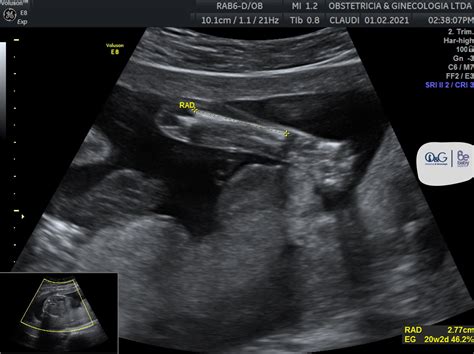

Las piernas

Se visualiza el fémur, el hueso más largo y fuerte del cuerpo. También se pueden observar la tibia y el peroné en la parte inferior de la pierna, así como la rodilla y el tobillo.